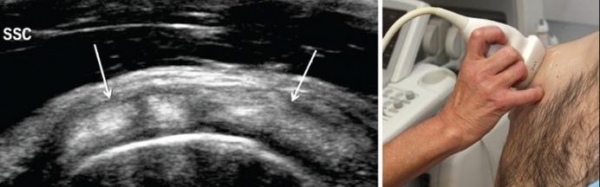

El nudo o contractura muscular es aquella contracción involuntaria de fibras musculares. La contracción involuntaria es exagerada y mantenida, por lo que al palpar la superficie de la piel donde se ha presentado la contracción se siente efectivamente un nudo.

El tamaño de un nudo o contractura muscular puede variar y depende del número de fibras musculares implicadas en la contracción involuntaria.